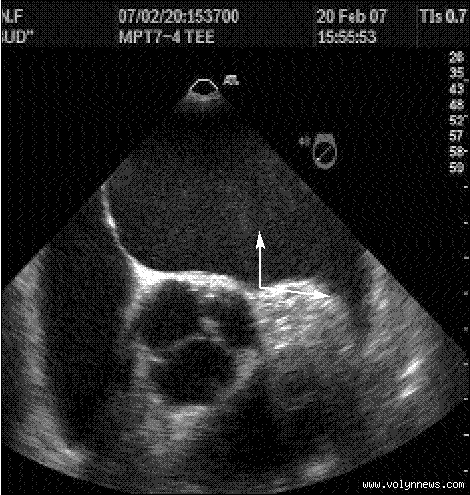

КЗ «Луцька міська клінічна лікарня», що знаходиться за адресою проспект Відродження, 13, уклала договір з купівлі із ПрАТ «УМТ». Згідно з ним, до кінця червня постачальник доправить трансезофагеальний датчик до ультразвукової діагностичної системи експертного класу вартістю 449000 гривень.